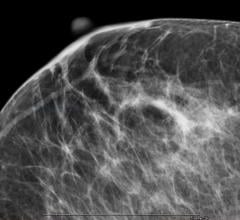

Mammography

Mammography is a breast imaging technique that uses X-rays to diagnose and locate tumors of the breasts.